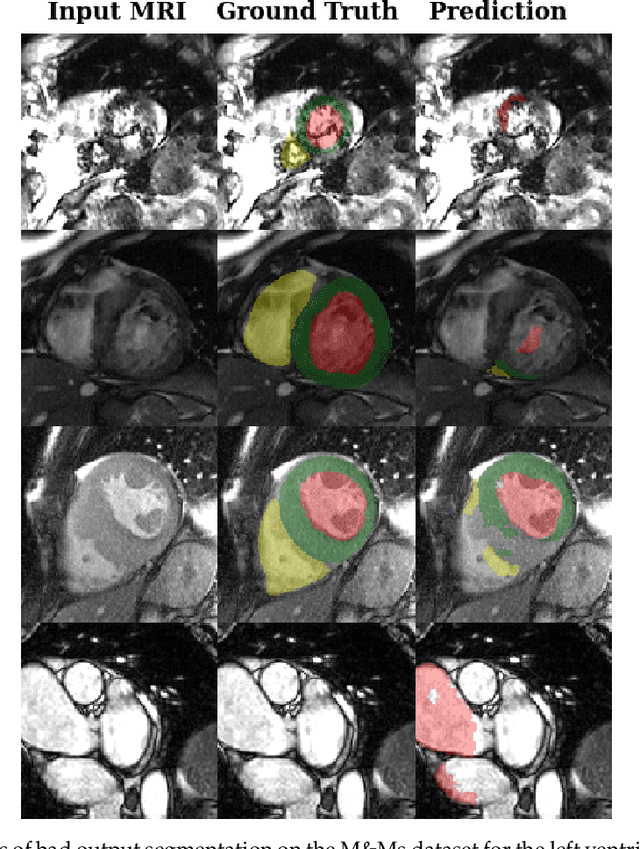

Abstract:Deep learning methods are the de-facto solutions to a multitude of medical image analysis tasks. Cardiac MRI segmentation is one such application which, like many others, requires a large number of annotated data so a trained network can generalize well. Unfortunately, the process of having a large number of manually curated images by medical experts is both slow and utterly expensive. In this paper, we set out to explore whether expert knowledge is a strict requirement for the creation of annotated datasets that machine learning can successfully train on. To do so, we gauged the performance of three segmentation models, namely U-Net, Attention U-Net, and ENet, trained with different loss functions on expert and non-expert groundtruth for cardiac cine-MRI segmentation. Evaluation was done with classic segmentation metrics (Dice index and Hausdorff distance) as well as clinical measurements, such as the ventricular ejection fractions and the myocardial mass. Results reveal that generalization performances of a segmentation neural network trained on non-expert groundtruth data is, to all practical purposes, as good as on expert groundtruth data, in particular when the non-expert gets a decent level of training, highlighting an opportunity for the efficient and cheap creation of annotations for cardiac datasets.